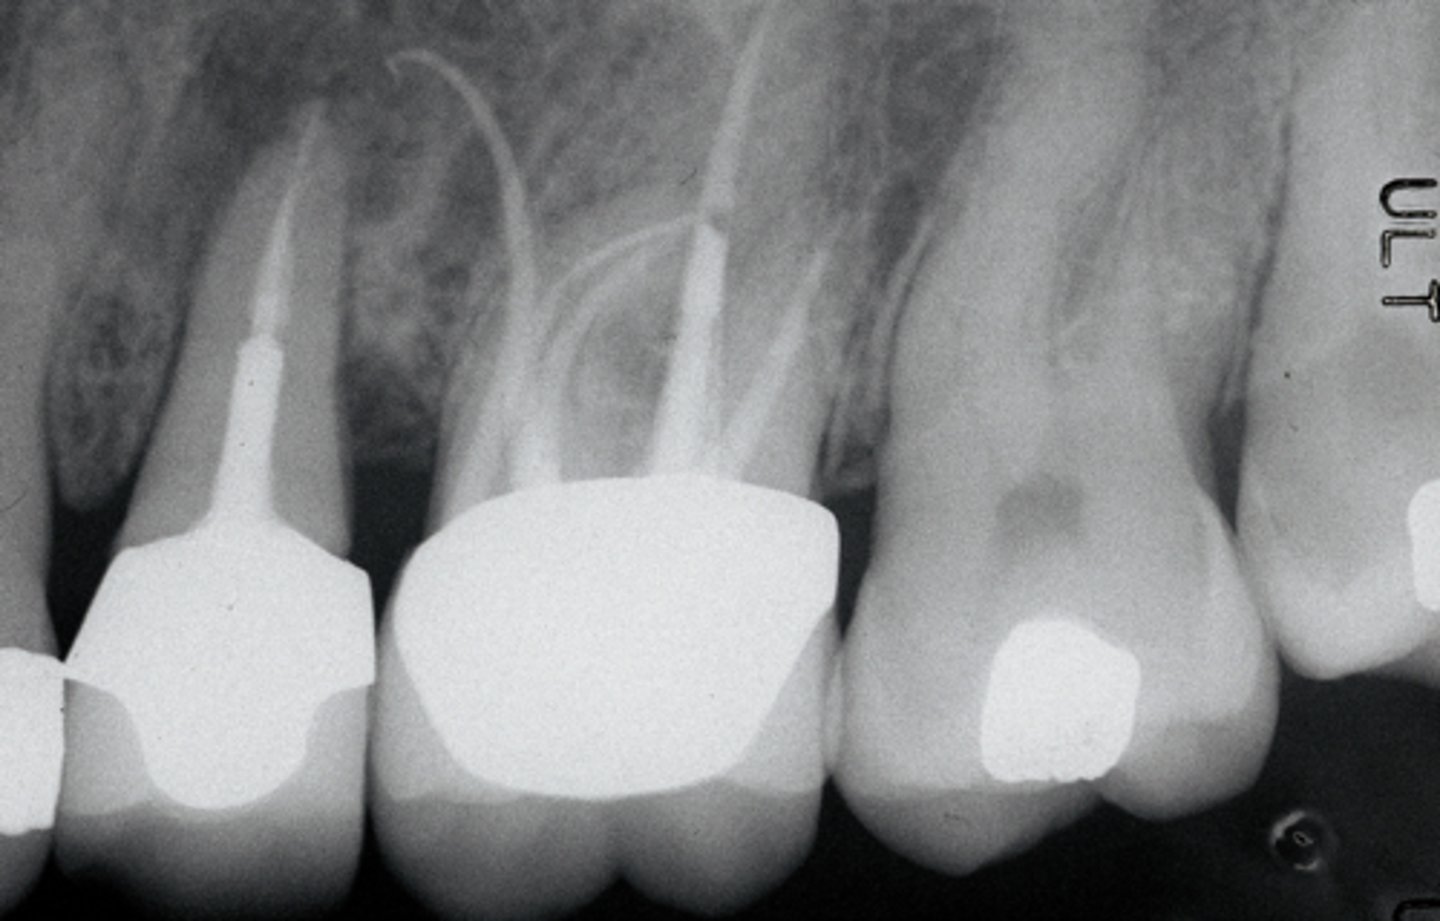

Check if missed MB2

RCT 10 years ago thru bridge

Sinus tract 3 years ago...apicoectomy done

Sinus tract returned.

What do we do?